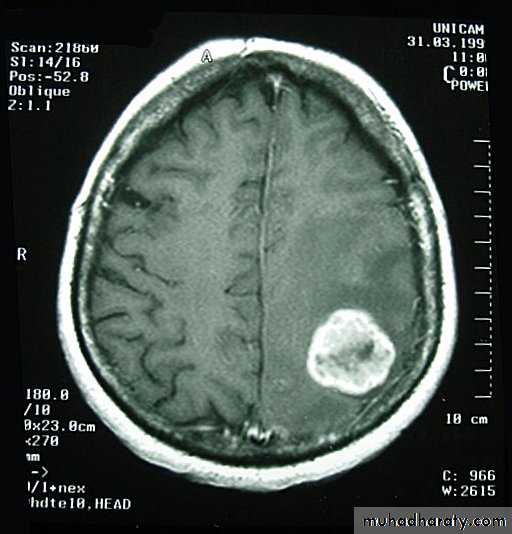

Metastatic Brain TumoursMRI